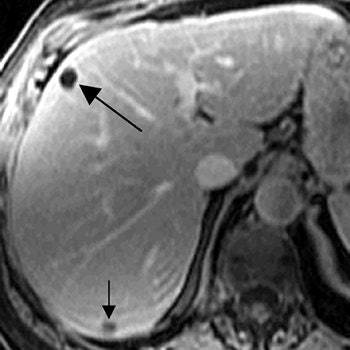

For this retrospective review, more than 5,000 women diagnosed with breast cancer between 2000 and 2003 at Sloan-Kettering were included. All MRI exams were done on 1.5-tesla scanners and the protocol included axial in-phase and opposed-phase T1-weighted gradient-echo images; axial fat-saturated fast spin-echo T2-weighted images; and dynamic multiphase gadolinium-enhanced axial T1-weighted gradient-echo images. CT scans were obtained on scanners with 7.0- to 7.5-mm collimation.

According to the results, 1.4% of the 5,440 women underwent MRI of the abdomen after initial diagnosis of breast cancer. Of those 76 patients, 50% had at least one hepatic lesion that was deemed too small to characterize on CT. The majority of these women (61%) had more than one lesion, including cysts and hemangiomas. In 21% of these patients, no lesion was found on MRI at the site that corresponded to at least one small hepatic lesion found on CT.

| A 71-year-old woman with invasive ductal carcinoma. Above, contrast-enhanced CT shows hepatic lesion (arrow) deemed too small to characterize. Below, contrast-enhanced T1-weighted MR image obtained 13 days after CT shows lesion (large arrow) in CT image is not enhanced, diagnostic of cyst. Lesion (small arrow) in posterior right lobe represents partial volume averaging of another cyst, which was evident in more caudal images (not shown). Patterson SA, Khalil HI, and Panicek DM, "MRI Evaluation of Small Hepatic Lesions in Women with Breast Cancer" (AJR 2006; 187:307-312). |

Overall, only 5% of the hepatic lesions were considered malignant based on the MR study, the authors noted. The majority of lesions was benign or remained indeterminate. "Thus in 95% of the women ... the results of MRI did not alter medical management because therapy is not changed for benign or indeterminate liver lesions.... MRI is not warranted," they concluded.